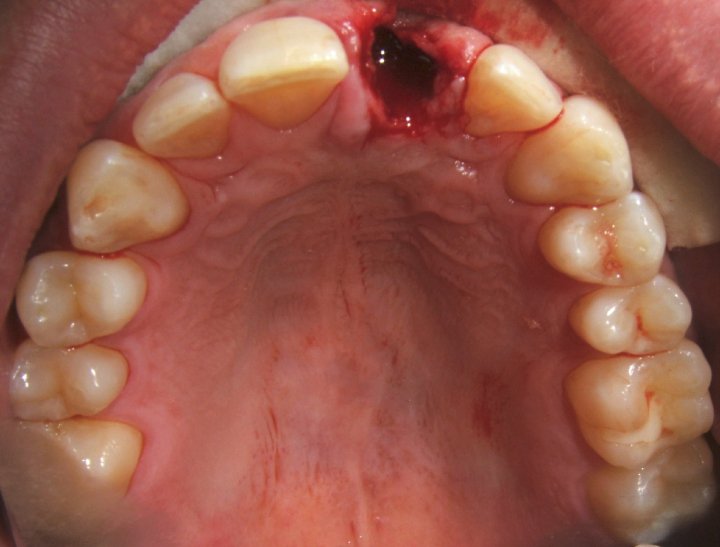

Immediate Implant Placement

One Year Post Op Healing Picture

Six Months Post Op Healing Picture